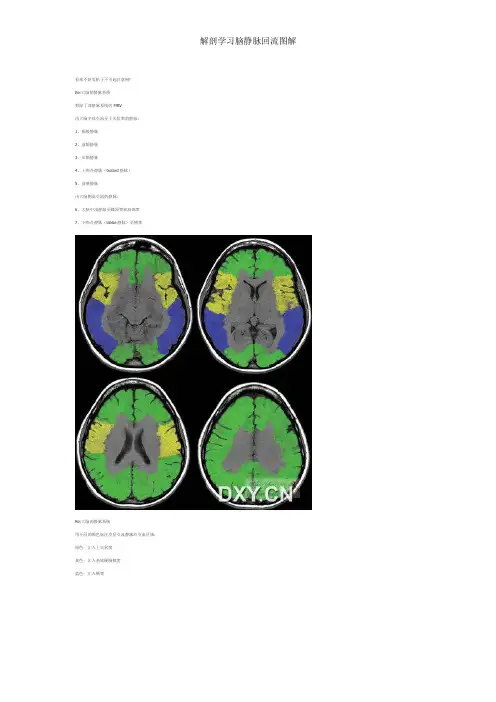

a. superior sagittal sinus,上矢状窦 r. parietal emissary vein,顶骨导静脉 c. straight sinus, 直窦 d. transverse sinus,横窦 o. occipital emissary vein,枕骨导静脉 f. the occipital sinus,枕窦 g. mastoid and condyloid emissary veins, 乳突和髁导静脉 m. vertebral veins,椎静脉 n. internal jugular vein,颈内静脉

C: cortical venous anastomoses among dural sinuses and cortical veins (Class II venous collaterals a. superior sagittal sinus,上矢状窦 j. the vein of Trolard,上吻合静脉 k. the vein of Sylvian (the superficial middle cerebral vein), 大脑中浅静脉 l. the vein of Labbe,下吻合静脉 d. transverse sinus,横窦 f. the occipital sinus,枕窦

D: deep and superficial medullary veins (Class II venous collaterals)

s. deep medullarydullary vein,浅表髓静脉

A: intra-extracranial venous collaterals (Class II venous collaterals)

B: the venous circle communicating bilateral venous blood flow (Class I venous collaterals);